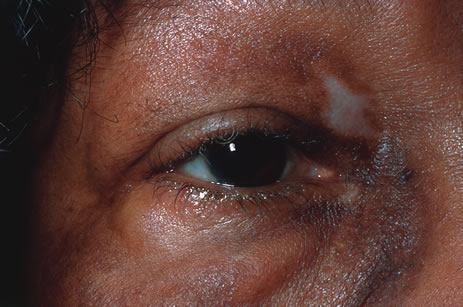

Reactivation of HSV may be precipitated by fever, trauma, menstruation, emotional stress, or systemic illness. Recurrent episodes of HSV type 1 and type 2 are generally preceded by several hours of burning, itching, and tingling before the skin vesicles appear. Systemic symptoms tend to be mild or absent, with the exception of recurrent adenopathy. The lesions appear similar to the primary infection and are frequently painful. The most frequent regional recurrences of HSV type 1 are on the vermilion border of the outer lip (herpes labialis) and in the eye (Fig. 2). Recurrences of HSV type 2 characteristically produce lesions on the penile shaft and glans in the male and on the labia and perineum in the female. Headache and aseptic meningitis are occasionally associated with a genital recurrence. Further recurrences may be seen at monthly or yearly intervals.

In primary ocular HSV infections, a severe follicular conjunctivitis with regional adenopathy is present. Vesicles may appear on the eyelid skin or lid margin, producing blepharitis (Fig. 3). Corneal involvement initially takes the form of a superficial punctate keratitis, which may progress to dendritic or geographic ulceration. Stromal infiltrates and uveitis are less common and relatively mild in primary disease. In uncomplicated cases, lesions usually heal completely in 2 to 3 weeks without scarring. Most cases of ocular HSV are recurrences. Recrudescent ocular herpes may take the form of dendritic or geographic ulcers, recurrent erosions, interstitial or disciform stromal keratitis, and anterior uveitis.3 HSV may also be an agent of retinitis and acute retinal necrosis (Fig. 4).